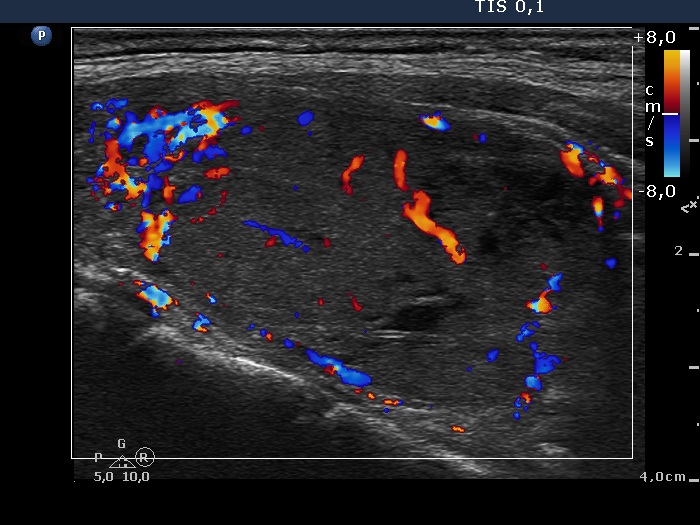

Differentiation of discrete lesions - case 441 (ultrasonographic picture 9)

Left lobe, horizontal scan, color Doppler mode. The nodule presents both perinodular and intranodular blood flow.